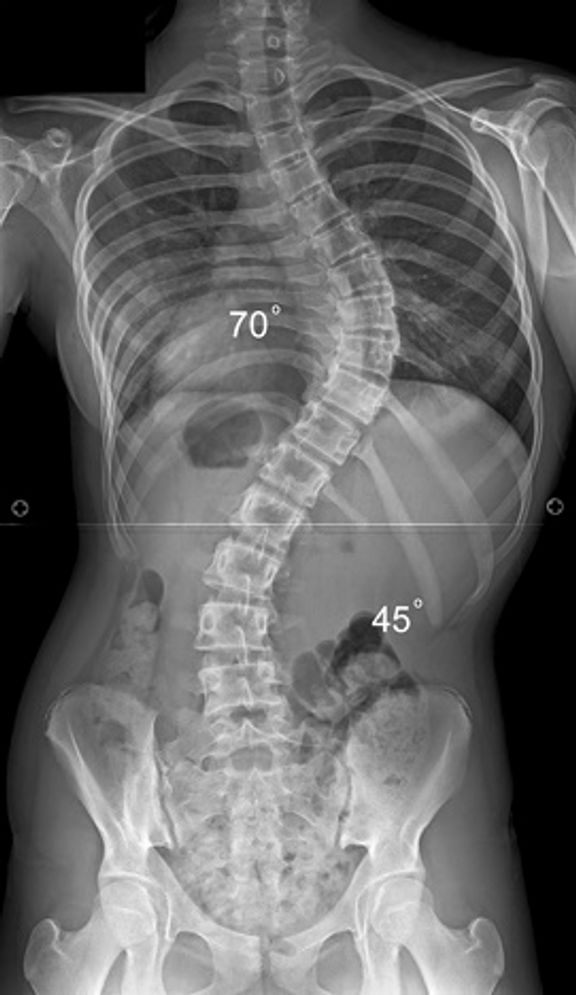

3. How is scoliosis diagnosed?

A physical exam is the first step in diagnosing scoliosis. During this simple exam, the pediatrician asks the patient to bend at the waist and checks the back for any left/right unevenness. Shoulder and pelvic symmetry are checked also for leg length or other developmental spinal issues.

Scoliosis is usually detected by family members or medical professionals during routine observation. Additionally, annual sport physicals may highlight changes in body shape in the growing child. If your pediatrician confirms signs consistent with scoliosis, your child may be referred for a scoliosis x‑ray to check the shape of their spine.

Some severe cases of scoliosis may require surgery to halt the progression of the spinal curvature and correct spinal balance. The most common type of scoliosis surgery is spinal realignment and fusion. Modern day techniques are very safe and effective at correcting scoliosis in the growing child.